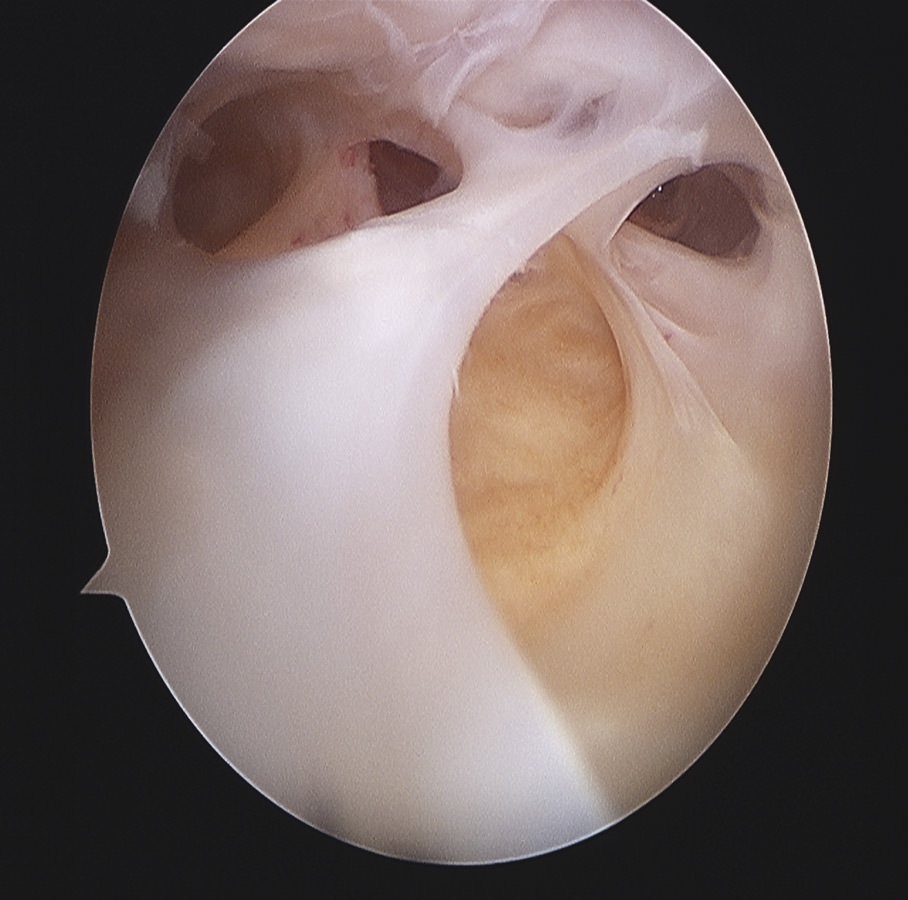

Siguiendo por los recesos lateral y medial (Figura 5) se llega a la zona suprapatelar, cuya fibrosis es la primera causa de limitación de la flexión (Figura 6). En este espacio hay que ser muy meticuloso para resecar con motor (Figura 7) y radiofrecuencia las adherencias, los nódulos, cíclopes (Figura 8), la fascia profunda del cuádriceps, con esqueletización de la cara anterior de fémur si es necesario, y liberar el alerón externo e interno, en función de la rótula: si está lateralizada (liberación solo lateral) o bien centrada (liberación lateral y medial), para facilitar el recorrido rotuliano. La limpieza de este espacio es fundamental para recuperar el máximo grado de flexión.

Figura 6. Bandas fibrosas articulares con disfunción patelofemoral y dolor anterior en prótesis de rodilla.